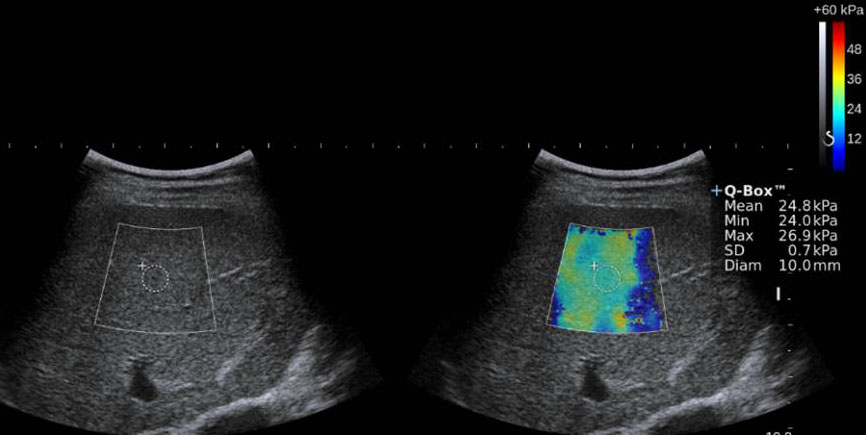

![]() |

☆写真の説明☆エラストグラフィを用いて肝臓の硬さをカラー表示で視覚的にみることが可能です。青色は正常で柔らかい肝臓で、赤色になるにつれ肝硬変に近い状態となります。 |